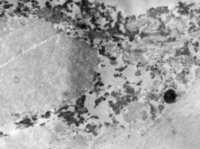

5-2-1 伤后第1天,表皮凝固性坏死,真皮浅层胶原纤维变性  HE×100